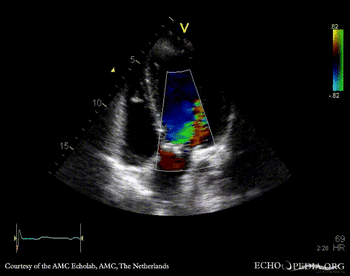

E00339.gif E00340.gif

PLAX: thickend aortic valve PLAX: Color Doppler, moderate aortic regurgitation